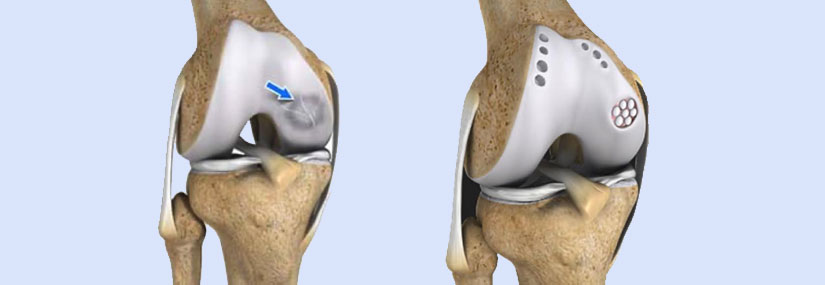

Cartilage Restoration:

• Microfracture: Small holes are made in the bone to stimulate the growth of new cartilage.

• Autologous Chondrocyte Implantation (ACI): Cartilage cells are harvested, cultured, and then implanted into the damaged area.

• Osteochondral Autograft Transplantation (OAT): Healthy cartilage and bone are taken from a non-weight-bearing area and transplanted to the damaged area.

• Osteochondral Allograft Transplantation: Similar to OAT, but the graft comes from a donor.